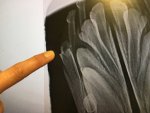

The area will still be sore, the remains of the tooth disintegrated as the vet tried to take it out, so more bone was cut away to remove the tooth safely and not disturb the capsule underneath. 4 months is difficult as ALL she wants to do is chew and carry things around, poor thing.